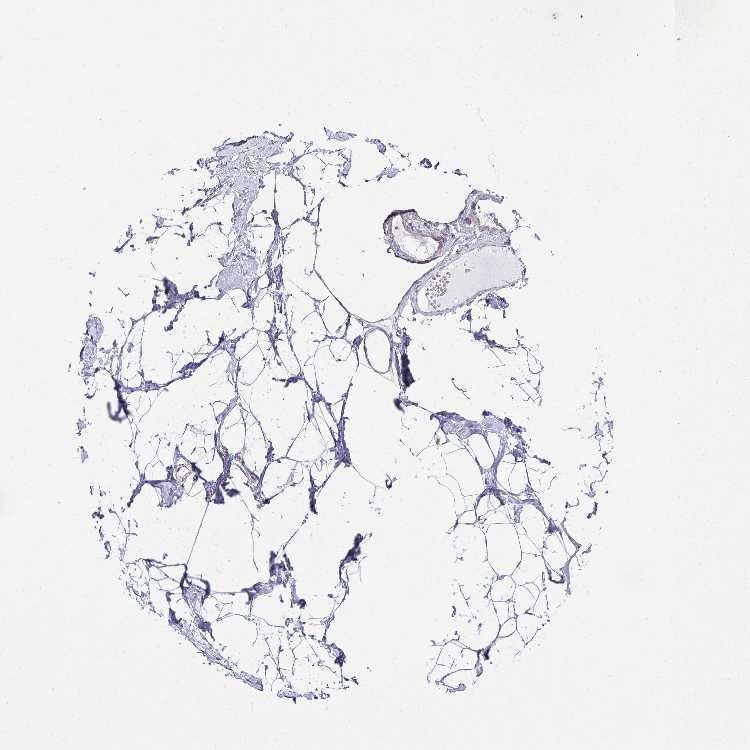

BREAST - Antibody stainingi

Antibody staining in the annotated cell types in the current human tissue is reported as not detected, low, medium, or high, based on conventional immunohistochemistry profiling in selected tissues. This score is based on the combination of the staining intensity and fraction of stained cells.

Each image is clickable and will lead to virtual microscopy that enables deeper exploration of all samples and also displays staining intensity scores, fraction scores and subcellular localization as well as patient and tissue information for each sample.

Antibody HPA047224Antibody HPA058546Antibody CAB008630

Adipocytes Not detectedNot detectedNot detected

Glandular cells LowNot detectedMedium

Myoepithelial cells Not detectedNot detectedMedium